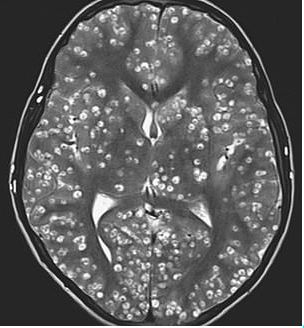

An MRI that was conducted on his brain to check the reason of his death showed cysts throughout his brain. It was spread like a wildfire in his brain. The cysts had converted into a life-threatening condition called neurocysticercosis which killed the young man.

Faridabad’s ESIC Medical College’s doctor Nishanth Dev submitted the case to The New England Journal of Medicine. He was the one who treated the patient who lost his life to neurocysticercosis.